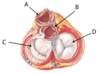

Which structure labels the pulmonary valve?

A

Which structure labels the aortic valve?

B